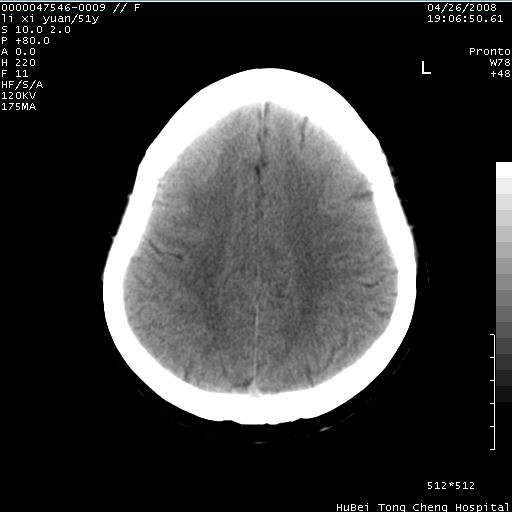

以下是引用余辉在2008-4-27 14:02:00的发言:[br]病灶位于中央沟前方?位于额叶?高密度灶,灶周水肿不明显,病灶似沿脑沟走行,强化明显,局部层面呈现环状强化,考虑1脑表面血管性疾病,如血管瘤,血管扩张,灶内血栓形成,其次考虑肿瘤如脑膜瘤、转移瘤,胶母等

以下是引用形影不离在2008-4-27 14:13:00的发言:[br]考虑胶质瘤可能性大,不排除慢性炎性肉芽肿。建议mri检查。